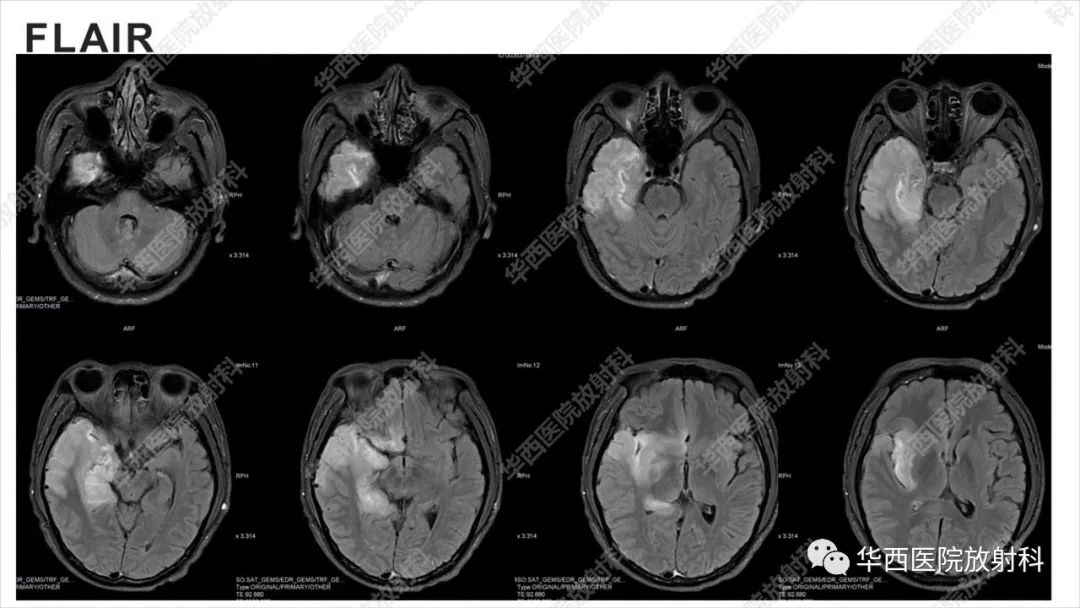

【病例】出血坏死性病毒脑膜脑炎1例CT及MR影像学表现和鉴别诊断-2